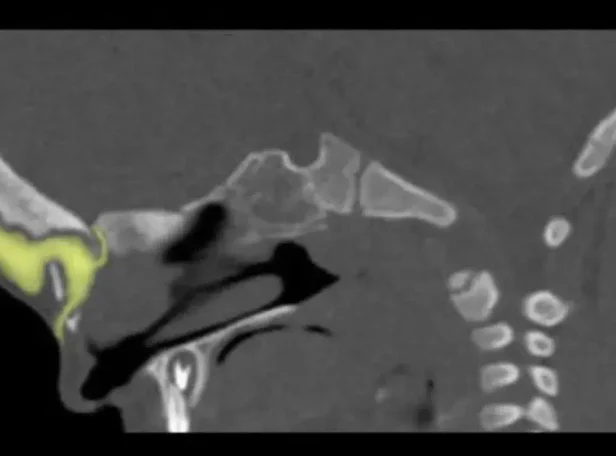

Иссечение дермальных синусов, дермоидных кист и перикраниальных синусовРазличают краниальный и спинальный дермальный синусы. Дермальный синус может заканчиваться как в мягких тканях, так и проникать в полость черепа или позвоночного канала. В последних случаях имеется высокий риск развития менингита. Лечение только хирургическое, проводится полное иссечение синуса. При распространении синуса до твердой мозговой оболочки свищ иссекается вместе с окружающим участком твердой мозговой оболочки. Дефект твердой мозговой оболочки герметично ушивается.